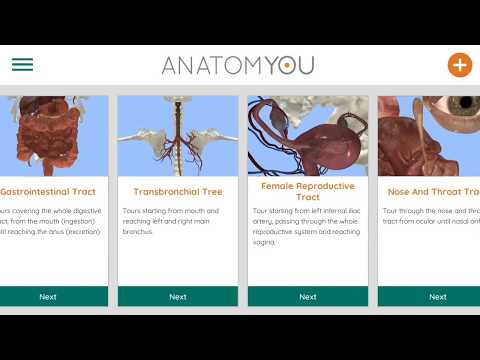

Korzystając z wirtualnej rzeczywistości, będziesz w stanie poruszać się wzdłuż struktur anatomicznych, stając się częścią ludzkiej anatomii: układu rozrodczego układu krążenia, oddechowego, trawiennego, moczowego, łzowego i żeńskiego.

Oferuje bezpłatny dostęp do niektórych tras nawigacji w prawie każdym z wymienionych systemów. Dodatkowa treść do kupienia jest oferowana w sekcji aplikacji w aplikacji.

Anatomyou VR może być używany w dwóch różnych trybach: Virtual Reality i Fullscreen.